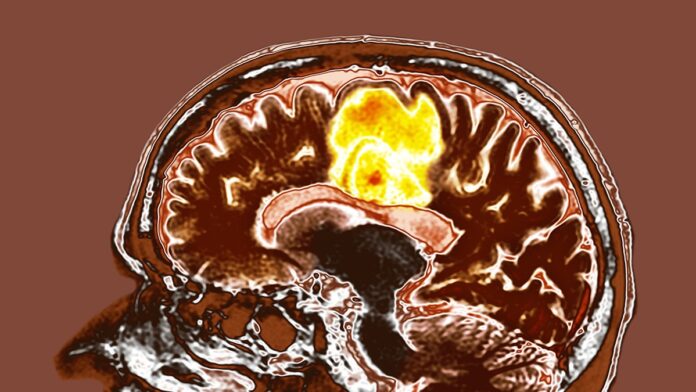

Wstępne badanie przeprowadzone w szpitalu Tata Memorial w Indiach sugeruje, że połączenie resweratrolu i miedzi może zaoferować nowe podejście do leczenia glejaka wielopostaciowego, jednej z najbardziej agresywnych postaci raka mózgu. Chociaż wstępne wyniki są zachęcające, naukowcy podkreślają, że potrzebne są długoterminowe dane, aby potwierdzić wpływ suplementów na przeżycie pacjentów.

Problem glejaka wielopostaciowego

Glejak wielopostaciowy jest niezwykle trudny w leczeniu ze względu na szybki wzrost i oporność na tradycyjne terapie. Obecne metody leczenia – chirurgia, radioterapia i chemioterapia – przedłużają życie, ale rzadko prowadzą do całkowitej remisji. To motywuje do poszukiwania innowacyjnych strategii, w tym badania potencjału łatwo dostępnych związków, takich jak resweratrol i miedź.